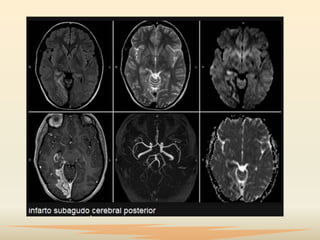

Diagnóstico

 Ante la sospecha deECV, se necesita identificar la lesión y

 La evaluación neuropsicológica de sujetos con daño

producido por ECV está enfocada en conocer las

funciones afectadas y depende del tipo de evento. En

el infarto cerebral se estudia por imágenes radiológicas

los aspectos topográficos de la lesión, especialmente

antes de las 24 horas del inicio del trastorno súbito.

 Los más utilizados son la tomografía computarizada,

la resonancia magnética y el estudio del flujo sanguíneo

regional cerebral.

Diagnóstico  Ante lasospecha deECV, se necesita identificar la lesión y su ubicación y obtener información sobre el estado estructural del parénquima del cerebro y su condición hemodinámica como consecuencia de la lesión.  La evaluación neuropsicológica de sujetos con daño producido por ECV está enfocada en conocer las funciones afectadas y depende del tipo de evento. En el infarto cerebral se estudia por imágenes radiológicas los aspectos topográficos de la lesión, especialmente antes de las 24 horas del inicio del trastorno súbito.

 Los másutilizados son la tomografía computarizada, la resonancia magnética y el estudio del flujo sanguíneo regional cerebral.